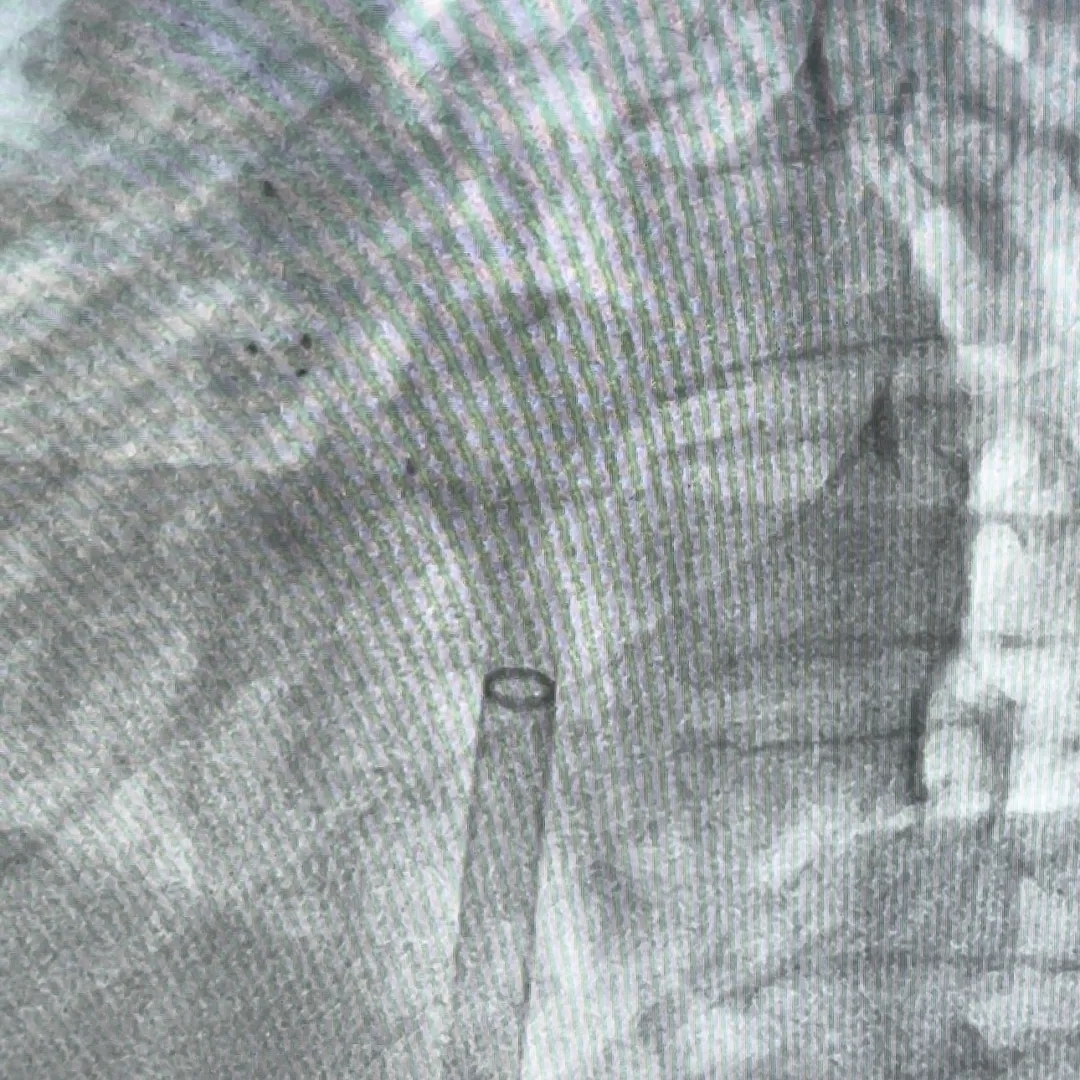

逆时针旋转钢缆释放封堵器,DSA下可见5个Mark点呈 “T”字型聚拢形态